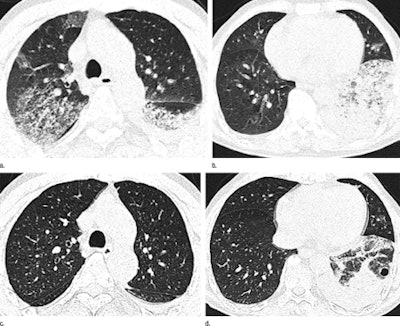

Axial thin-section CT images in 65-year-old man with H7N9 influenza. Top row, initial images obtained at admission show extensive GGOs and consolidation. Bottom row, images at seven-day follow-up show complete resorption of the lesion in the right upper lobe and partial resorption in the left lower lobe with a round cystic change. Images republished with permission of RSNA from Radiology July 2, 2013.

Axial thin-section CT images in 65-year-old man with H7N9 influenza. Top row, initial images obtained at admission show extensive GGOs and consolidation. Bottom row, images at seven-day follow-up show complete resorption of the lesion in the right upper lobe and partial resorption in the left lower lobe with a round cystic change. Images republished with permission of RSNA from Radiology July 2, 2013.Additional findings included consolidations, bronchograms, and interlobular septal thickening (each in 11 patients). Less common were centrilobular nodules (seven patients), cystic changes (four patients), and bronchial dilatation and subpleural linear opacities (each in three patients), Wang and colleagues wrote.